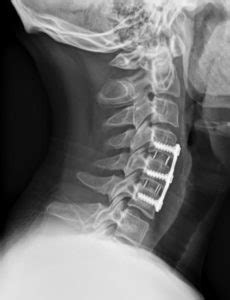

Joined 7 mo ago 1 Posts. With fusion at three or more levels of the spine there is a significant risk that the surgery will not improve the patients pain. An X-ray of the neck including the cervical vertebrae.

All had 3-level anterior cervical discectomy and fusion with tricortical iliac crest autograft 4 cases fibular ring allograft 38 cases or titanium cage 4 cases. Allografts and cages were filled with iliac crest autograft. This operation in performed thru the front portion of the neck from either the right or left side.

Post Operative X Ray Image Lateral Projection Showing Anterior Download Scientific Diagram